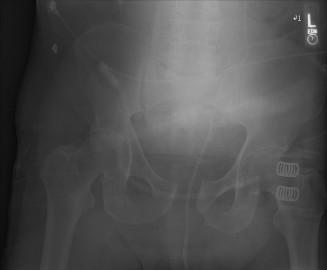

A 29-year-old woman arrives to the emergency department after jumping from the second story of a burning buil…